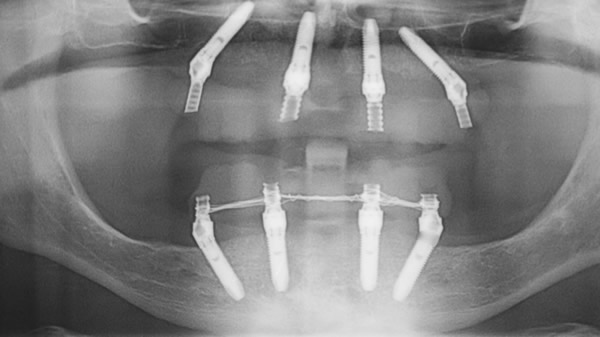

L’implantologia a carico immediato all on four utilizza impianti dentali inclinati tra i 30 ed i 45 gradi allo scopo di assicurare un solido appoggio alla protesi dentale.

Proprio per questo, l’implantologo, prima di attuare l’intervento prenderà in considerazione l’anamnesi del paziente e lo sottoporrà ad esami specifici tra cui una tac, una radiografia panoramica, un Ecg, esami del sangue e quant’altro.